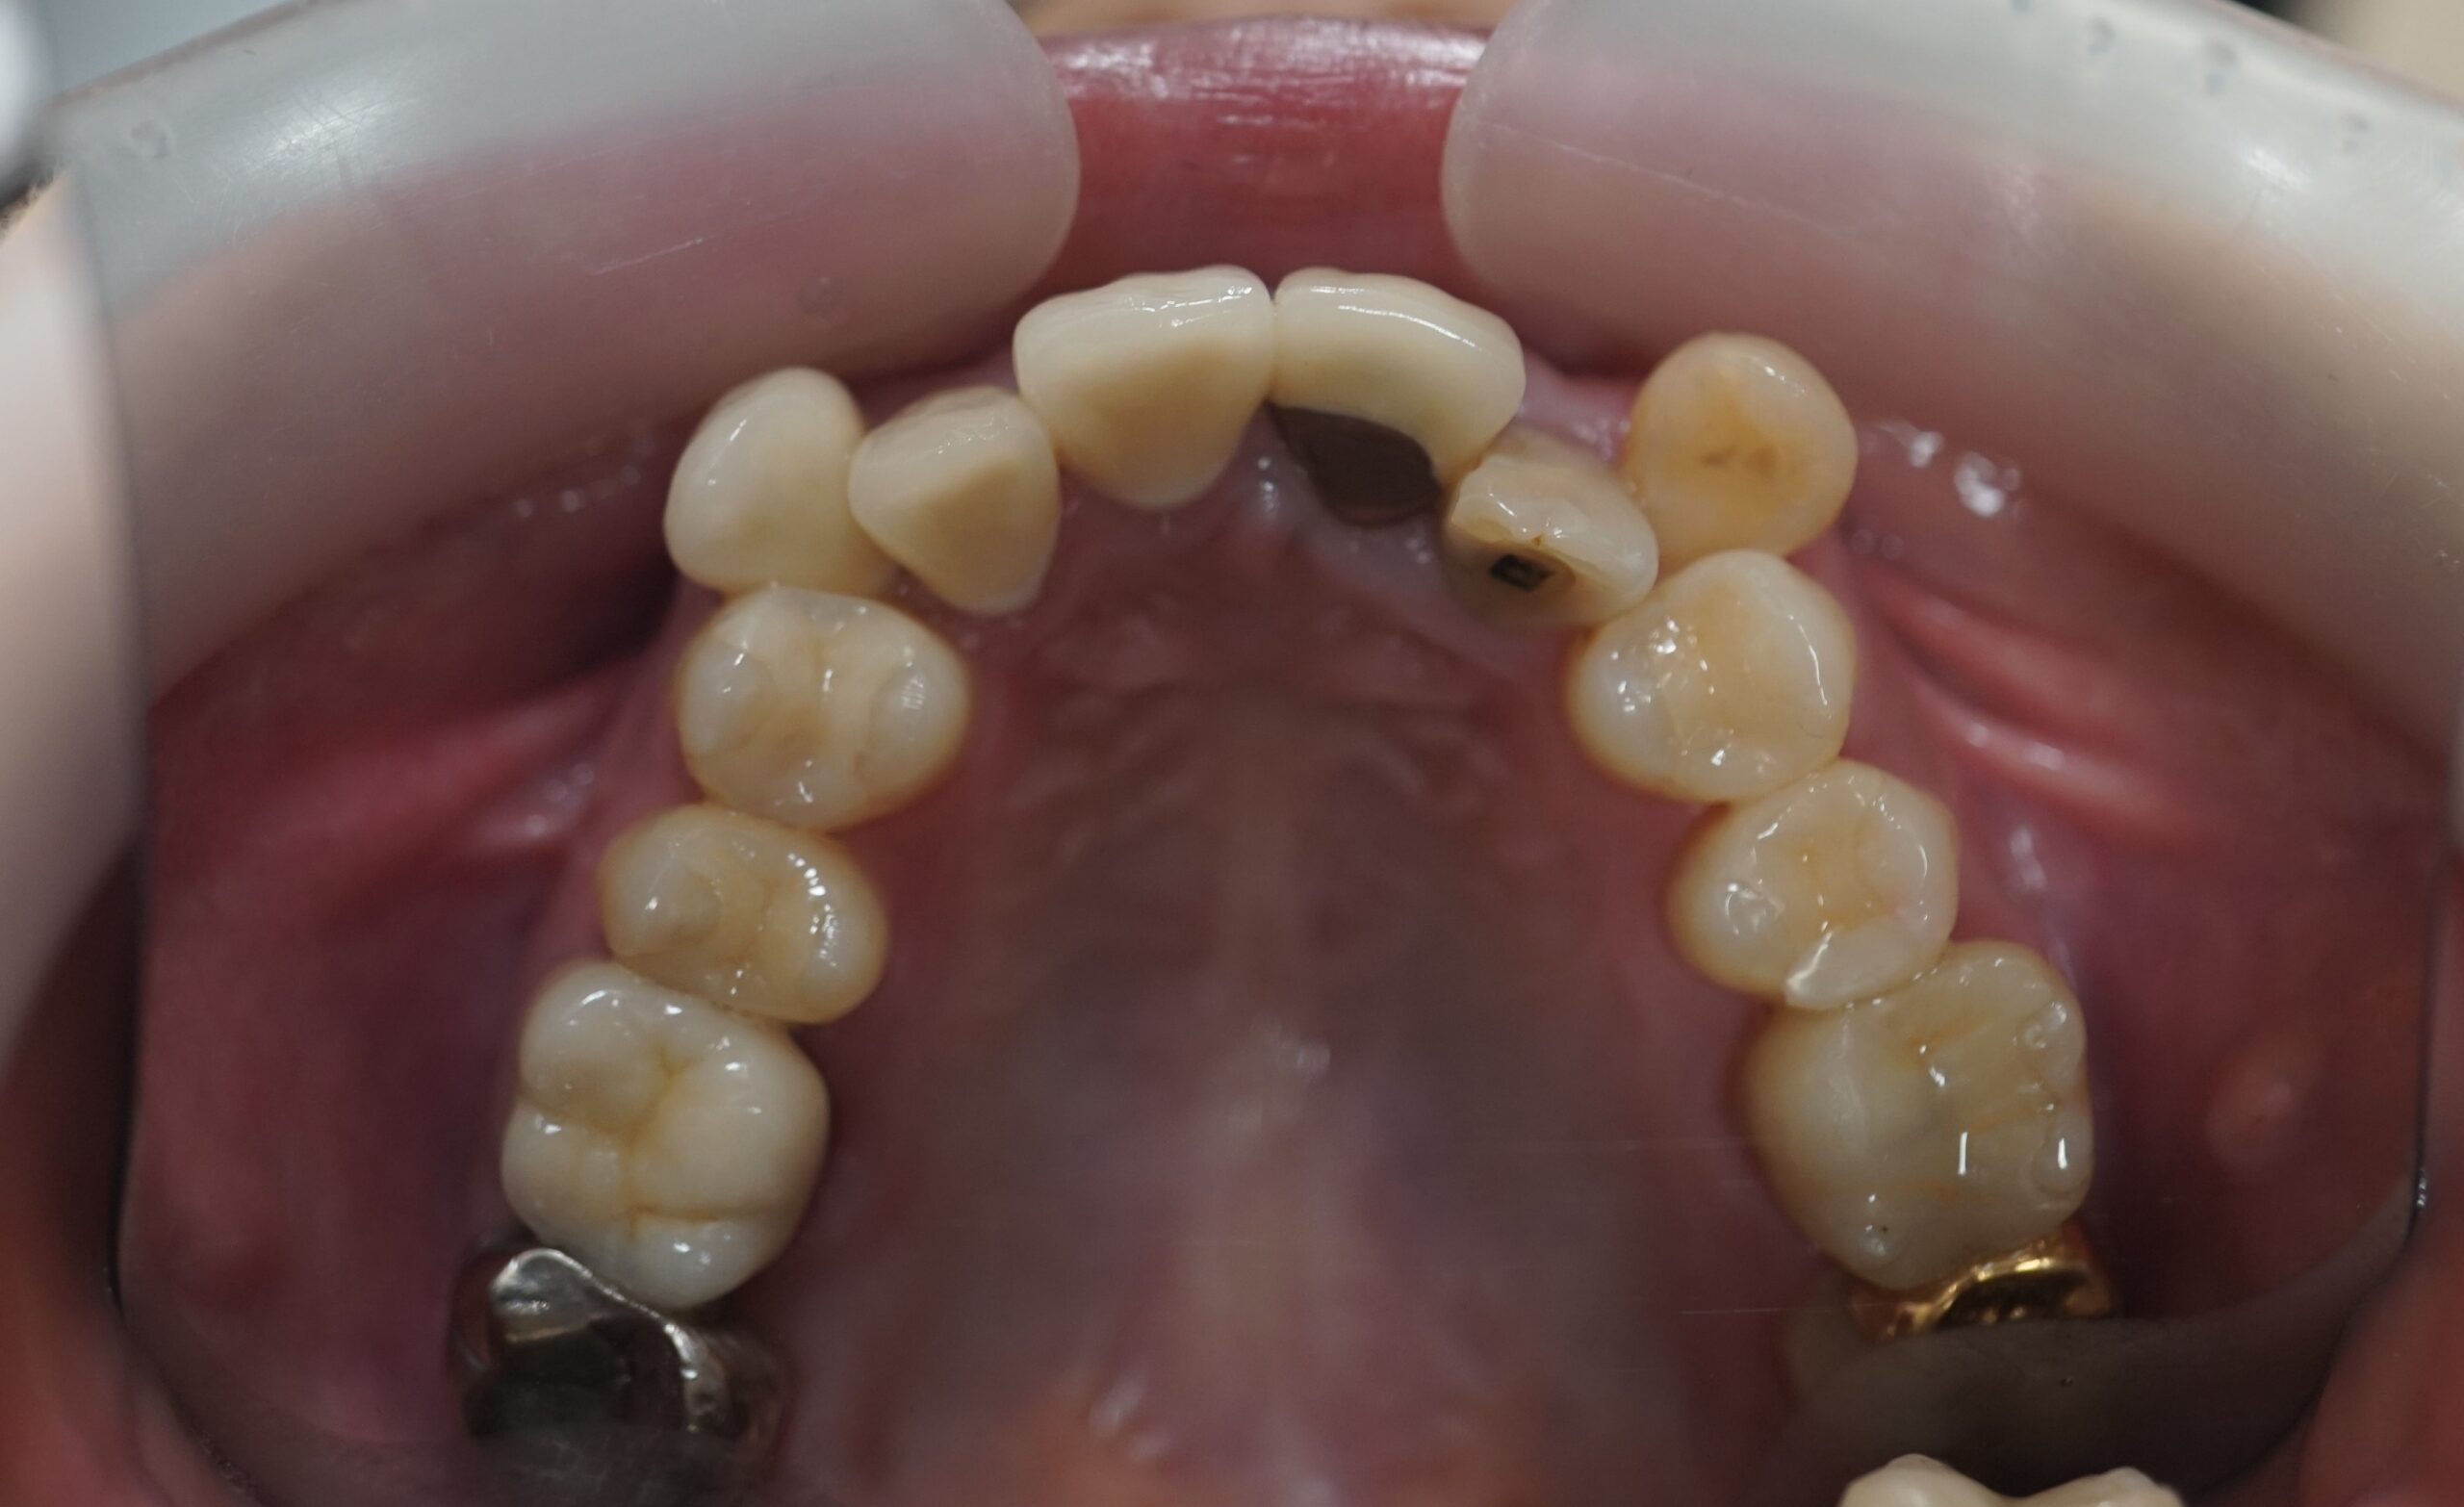

◾️治療前の状態(Before)

上顎前歯部に八重歯(叢生)が見られ、犬歯を含む前歯が歯列から外側にずれて生えている状態。

歯の重なりにより歯列のアーチが乱れ、八重歯が目立つことに加え、歯磨きもしにくい状況でした。

◾️治療後の状態(After)

インビザライン矯正により、前歯の歯の重なりが解消され、犬歯を含む前歯が歯列内にきれいに収まりました。

歯列のアーチも整い、八重歯による突出感も改善しています。

◾️治療内容の概要

治療方法:マウスピース型矯正装置(インビザライン)

治療期間:8ヶ月

◾️矯正治療に伴うリスク・注意点

歯列矯正中に伴う疼痛・咬合痛・う蝕・歯肉退縮などのリスクがあります。治療期間や費用については個人差があります。